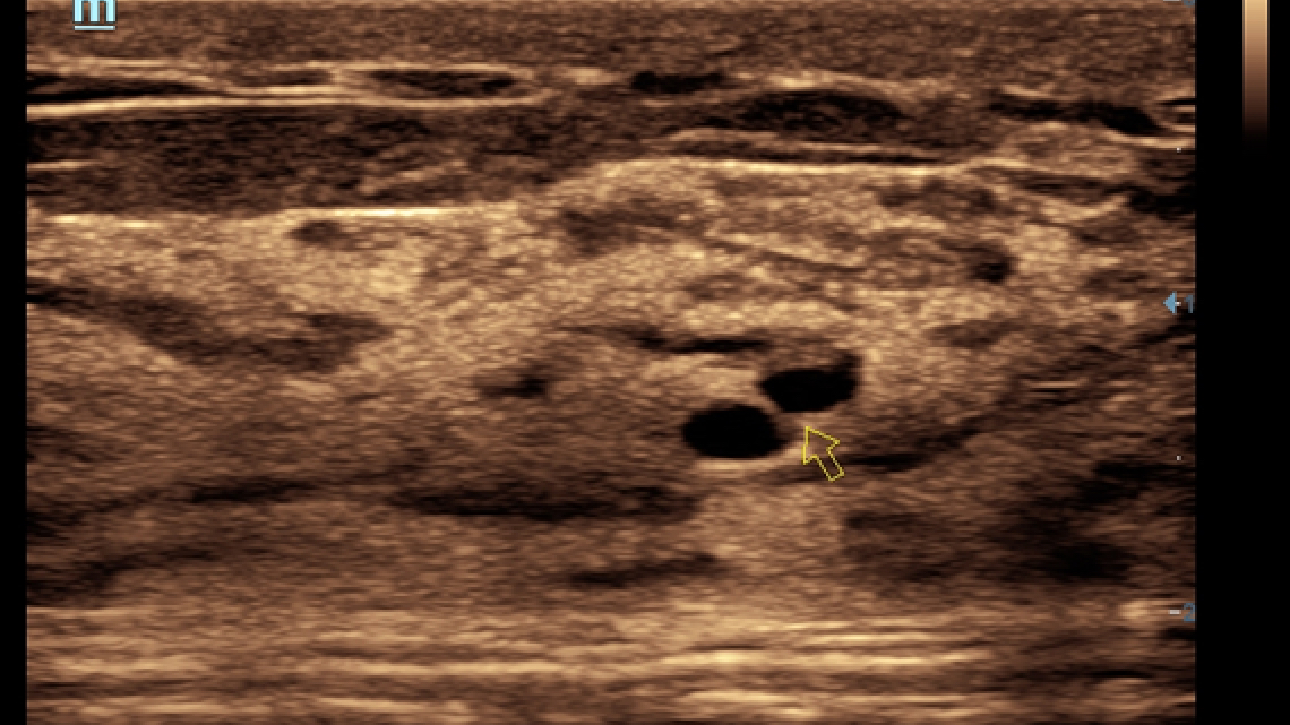

X-Insight, daha geli?mi? g?rĂŒntĂŒler elde etmek i?in kapsaml? bir ??zĂŒmdĂŒr.

Mindrayâin yeni ??zĂŒmĂŒ, geli?en en yeni ultrason teknolojileri ile birlikte, mĂŒ?terilerin g?rĂŒ?lerini klinik gerekliliklerle tam anlam?yla birle?tiren bir ??zĂŒmdĂŒr. Taptaze bir ruhla, gelece?e odaklanarak ve s?n?rs?zl???n pe?inde ko?arak, artan ?l?eklenebilirlikte sĂŒrekli olarak geli?en bir ??zĂŒmdĂŒr.

?ok y?nlĂŒ bir partner olarak, X-Insight'l? DC-60 Exp, her y?nĂŒyle gĂŒnlĂŒk klinik uygulamay? kolayl?kla ve belirsizlik olmadan y?netmenize yard?mc? olacak kapsaml? bir ??zĂŒm sunar.

MĂŒ?teri gereksinimlerine y?nelik g?rĂŒ?ler temelinde, X-Insight'l? DC-60 Exp, eXpress Clarity, eXceptional Intelligence ve eXceeding Experience ile gĂŒ?lendirilerek, hassas g?rĂŒntĂŒlemeyle yĂŒksek verimlilik sa?layacak ?ekilde tasarlanm??t?r.